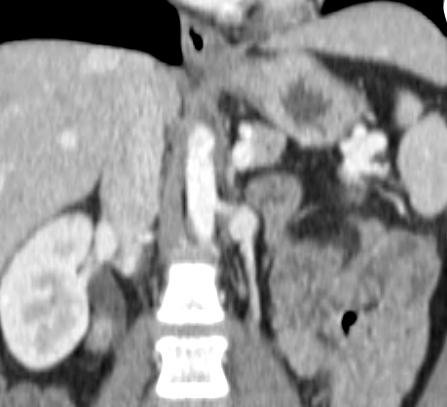

Case 3-F/U

In this retrospective study consisting of three patients, balloon-occluded retrograde transvenous obliteration (BRTO) can be a successful alternative treatment of gastric varices in patients with portal vein thrombosis who are ineligible for TIPS